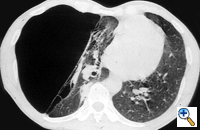

The preoperative work-up should always include clinical and functional evaluation (arterial blood gas analysis and pulmonary function tests with plethysmography), chest x-ray (Figure 6), computed tomography (Figure 7), and V/Q scan (Figure 8). Pulmonary angiography (Figure 9) has been reported to show some advantages in evaluating the underlying lung; however, it is not routinely performed.